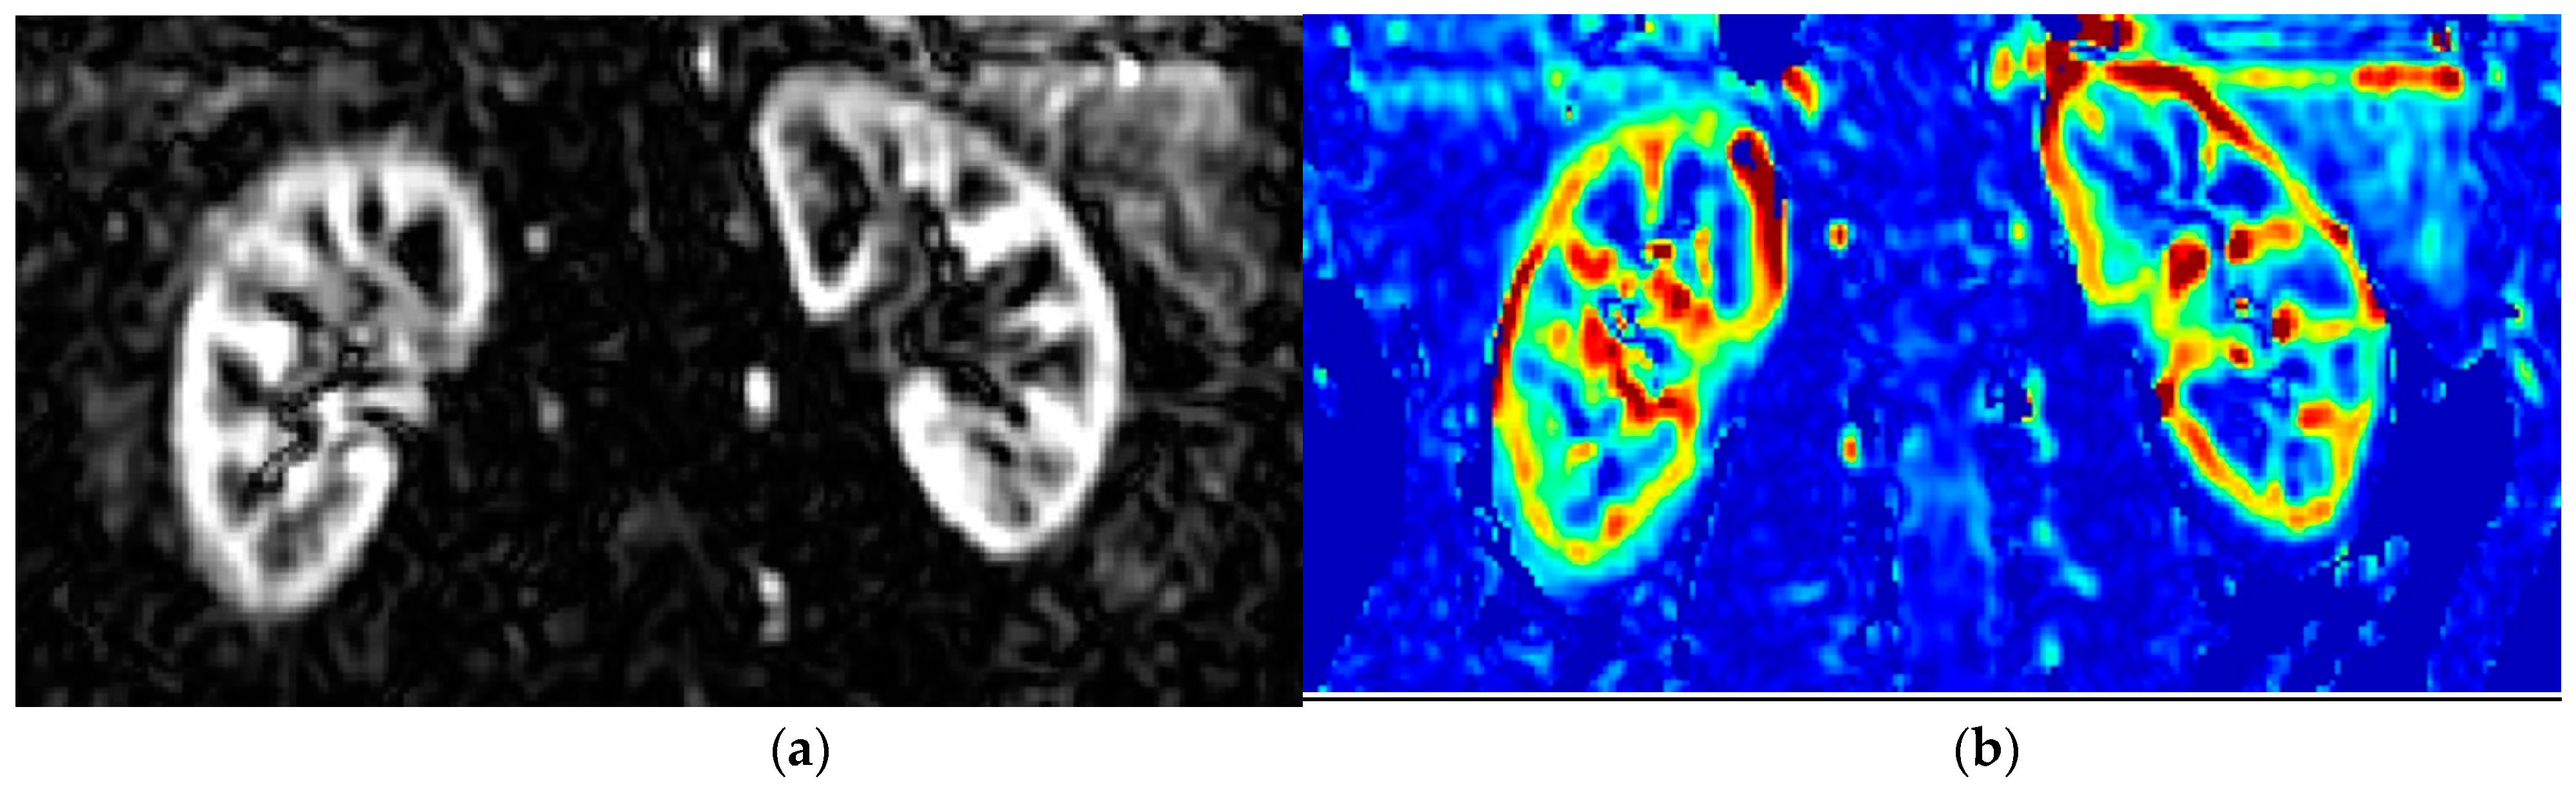

1.2. Principles of MRI-Measurement of Renal Perfusion (ASL) and Oxygenation (BOLD)

1.3. Renal Perfusion and Renal Oxygenation Using MRI